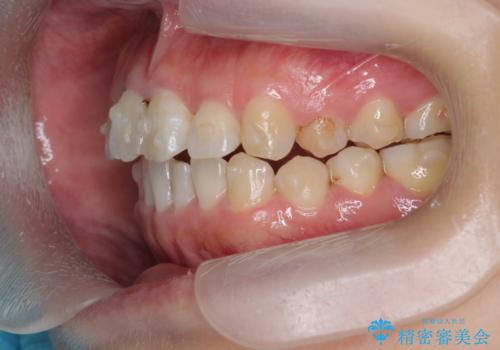

- 前歯のねじれを改善したい、と矯正治療を希望され来院されました。

上下の歯のがたつきを改善するマウスピース矯正治療と、下顎に見られる大きな骨隆起を外科的に除去する治療計画を進めていきます。

歯並びが改善したとともに、骨隆起を除去したことで舌をしまうスペースも増え安定した口腔内環境を確立することができました。